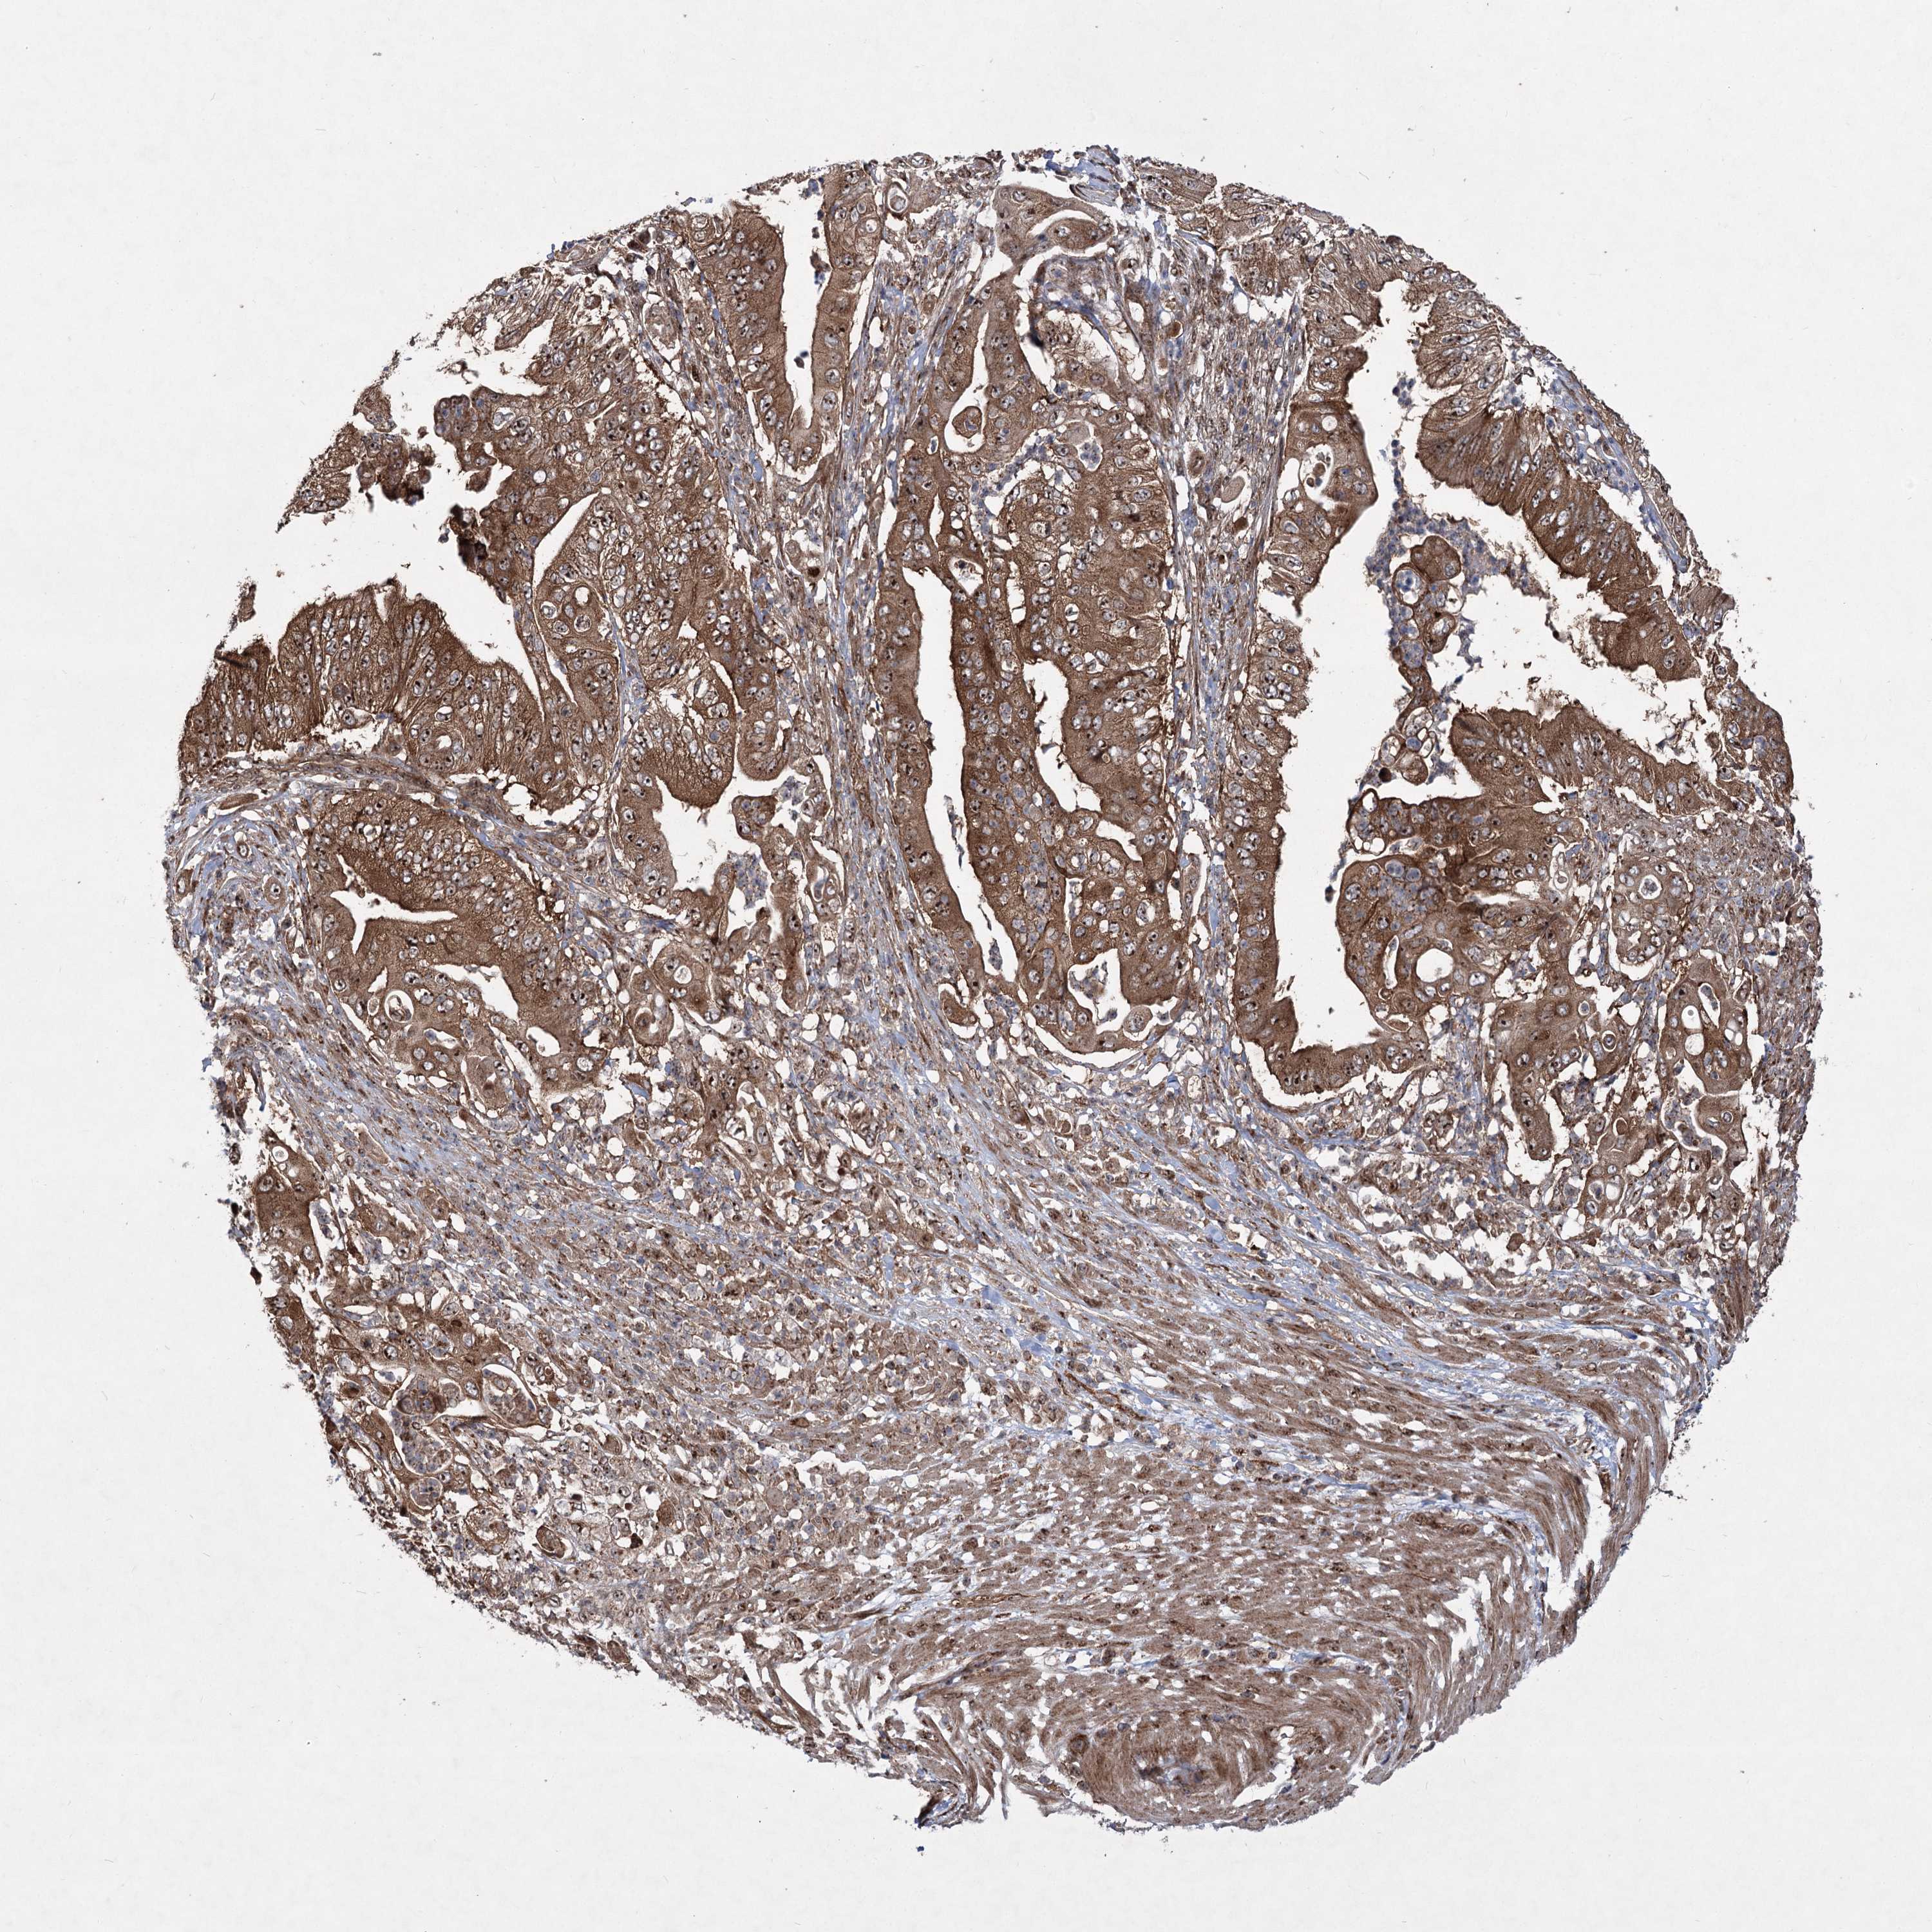

PANCREATIC CANCER - Protein expressioni

A mouse-over function shows sample information and annotation data. Click on an image to view it in a full screen mode. Samples can be filtered based on level of antibody staining by selecting one or several of the following categories: high, medium, low and not detected. The assay and annotation is described here.

Note that samples used for immunohistochemistry by the Human Protein Atlas do not correspond to samples in the TCGA dataset.

Antibody stainingi

Antibody staining in the annotated cell types in the current human tissue is reported as not detected, low, medium, or high, based on conventional immunohistochemistry profiling in selected tissues. This score is based on the combination of the staining intensity and fraction of stained cells.

Each image is clickable and will lead to virtual microscopy that enables deeper exploration of all samples and also displays staining intensity scores, fraction scores and subcellular localization as well as patient and tissue information for each sample.

Antibody HPA037898

Antibody HPA037899

Staining

High

Medium

Low

Not detected

Intensity

Strong

Moderate

Weak

Negative

Quantity

>75%

75%-25%

<25%

None

Location

Nuclear

Cytoplasmic/membranous

Cytoplasmic/membranous,nuclear

Adenocarcinoma, NOS